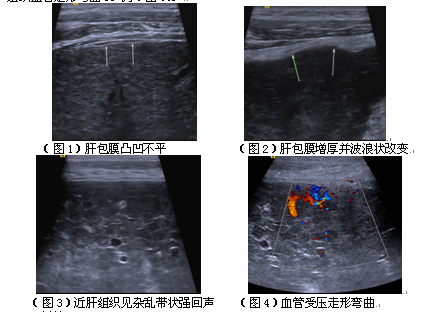

随着人民生活的不断改善,肥胖、高血脂、高血压的病人越来越多,脂肪肝的人随处可见,下面就脂肪肝的超声检查方法及检查内容给大家简要介绍。检查方法:应用凸阵或线阵探头,探头频率···...